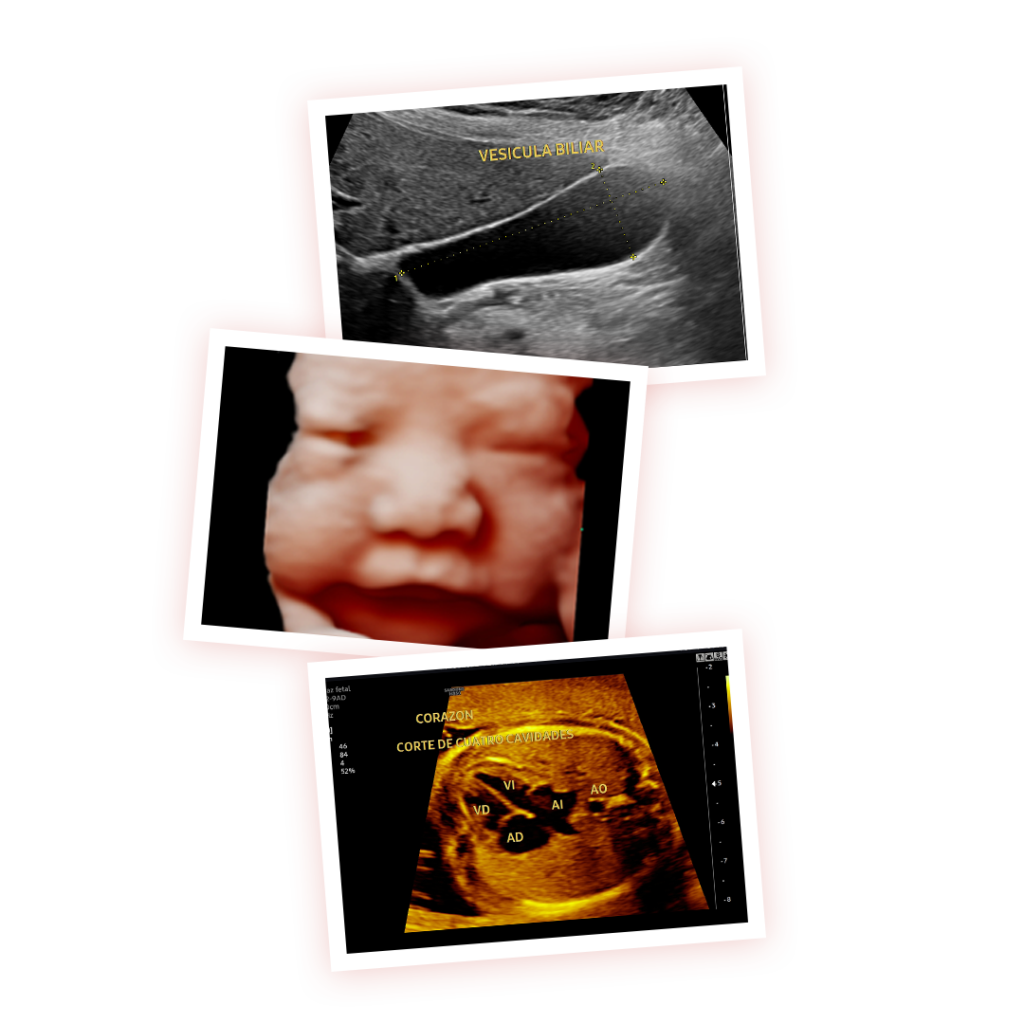

Ecografías Obstetricas

Ecografías Ginecologicas

Ecografias Partes Pequeñas

Ecografías Urologicas